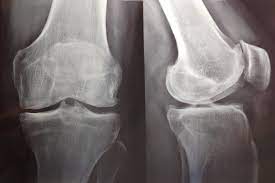

En este estudio de utilización de medicamentos se encontró que entre los pacientes daneses con artrosis de rodilla grave, la prevalencia y el uso total de opioides se duplicó durante los 5 años anteriores a al reemplazo de rodilla. Además, el 10% de la población de estudio fue responsable del 90% de los opioides utilizados. Eur J Clin Pharmacol, 13 de junio de 2022